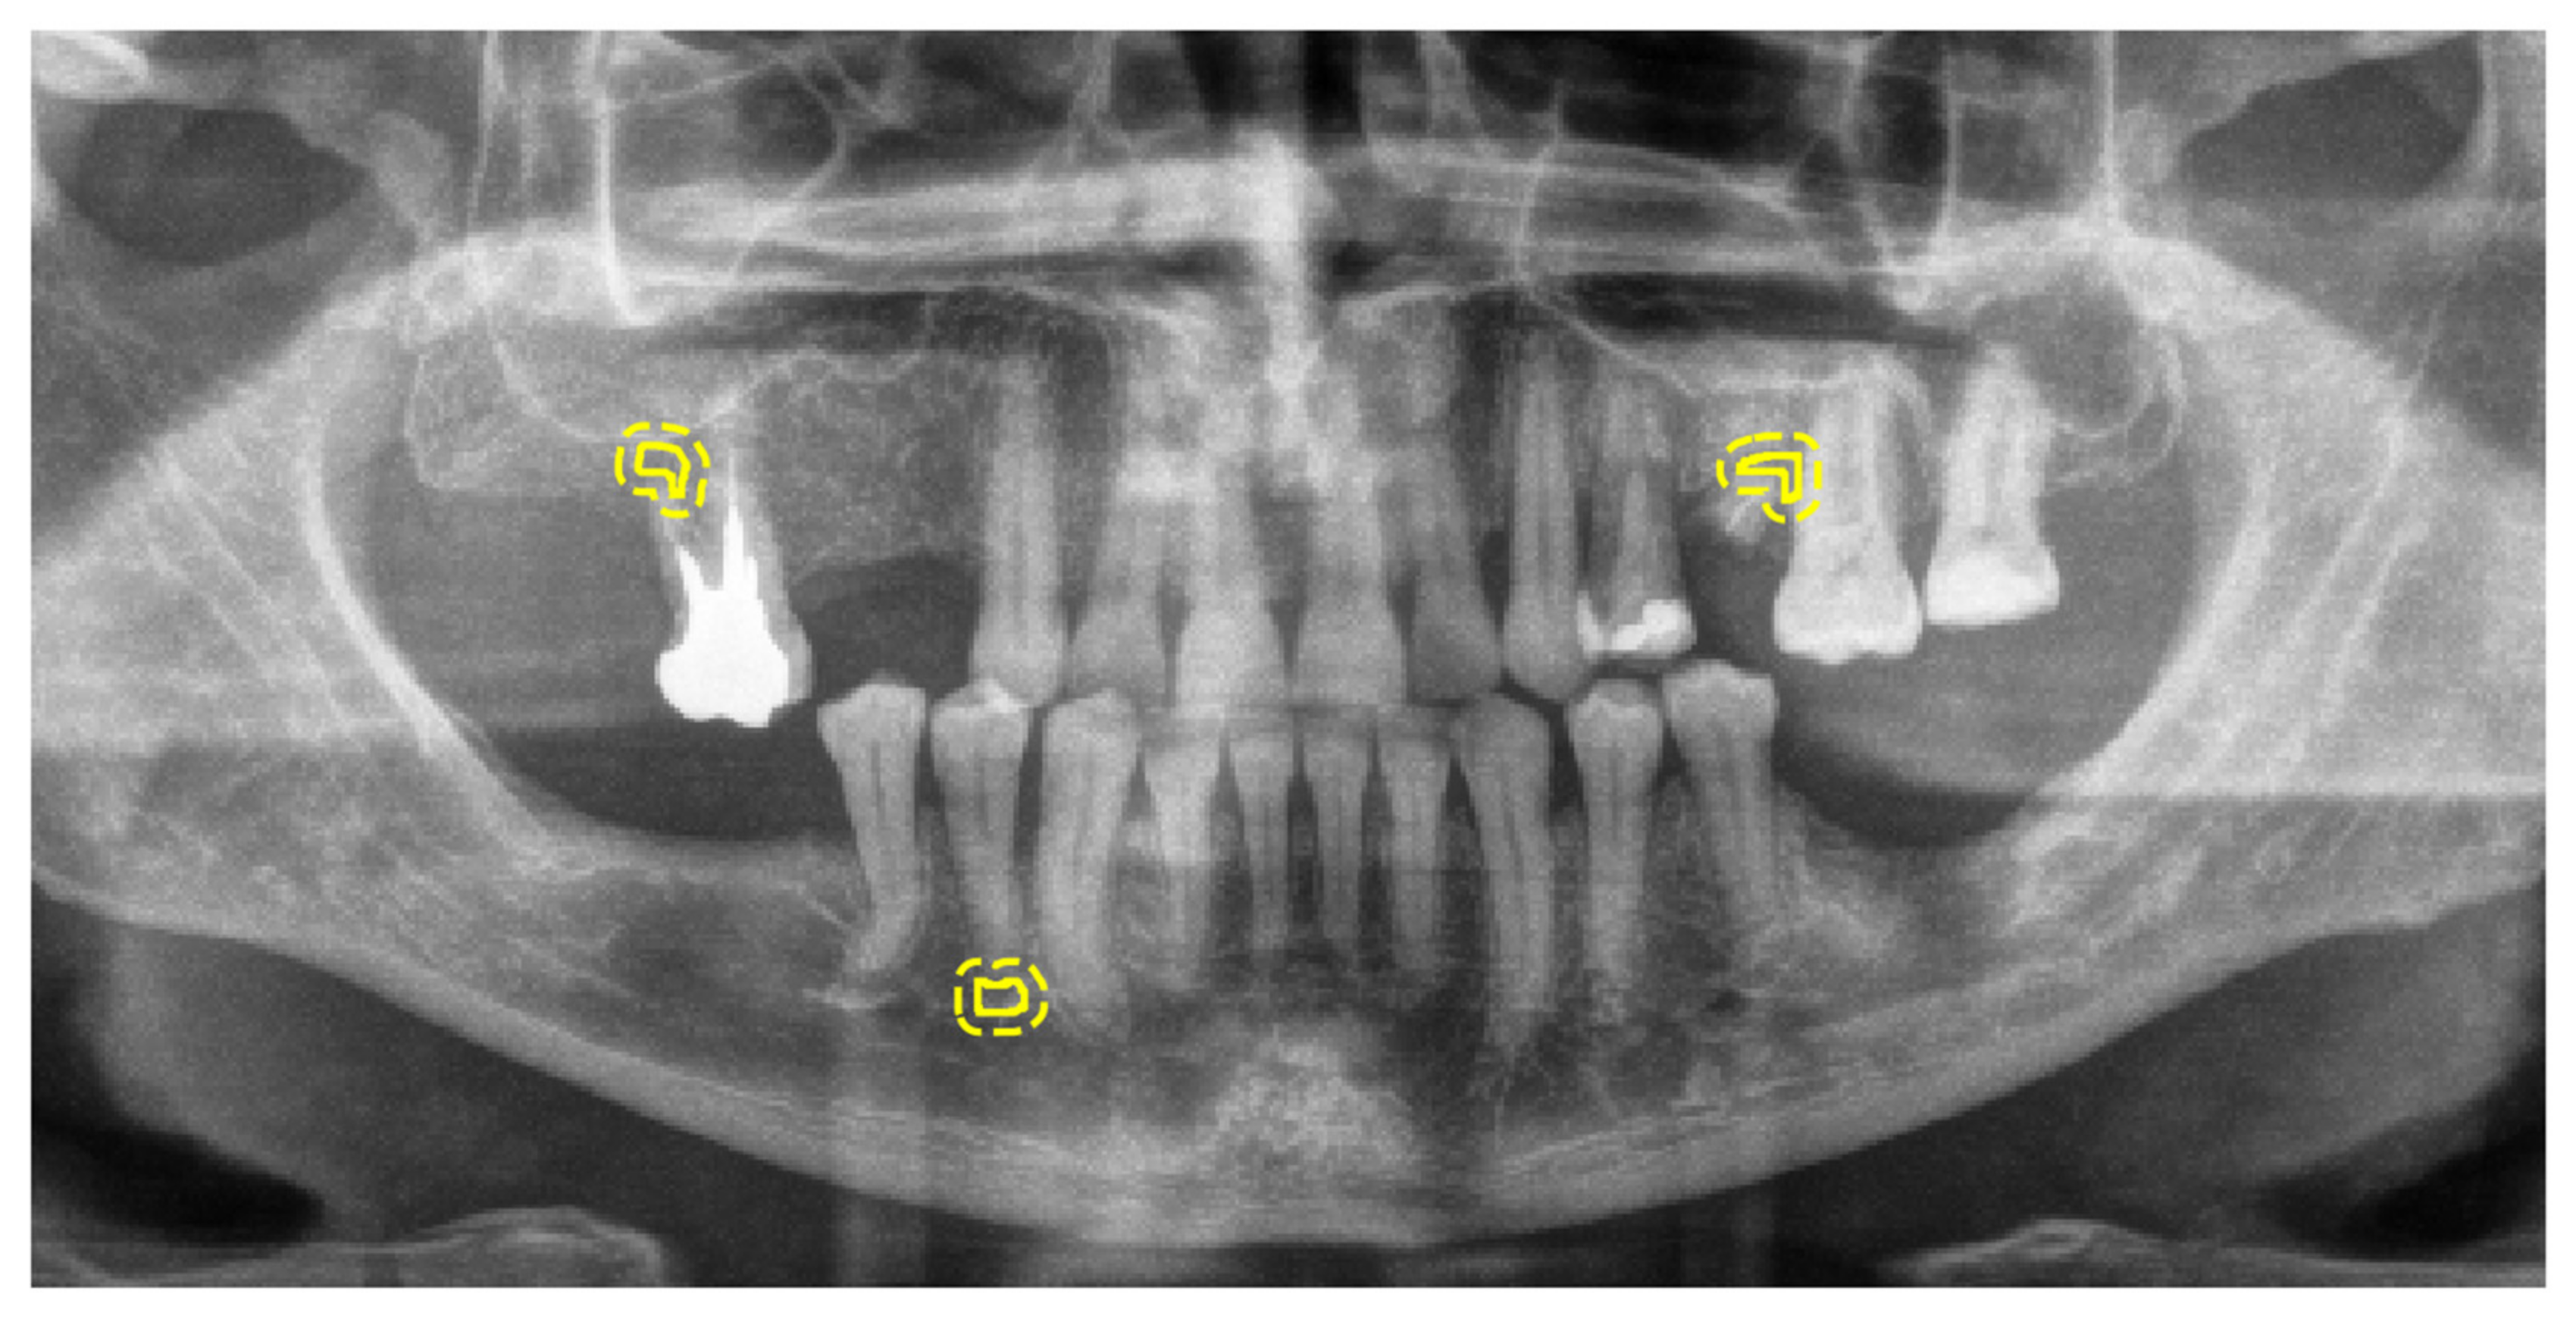

3.2. Performance of the Deep Learning Algorithm